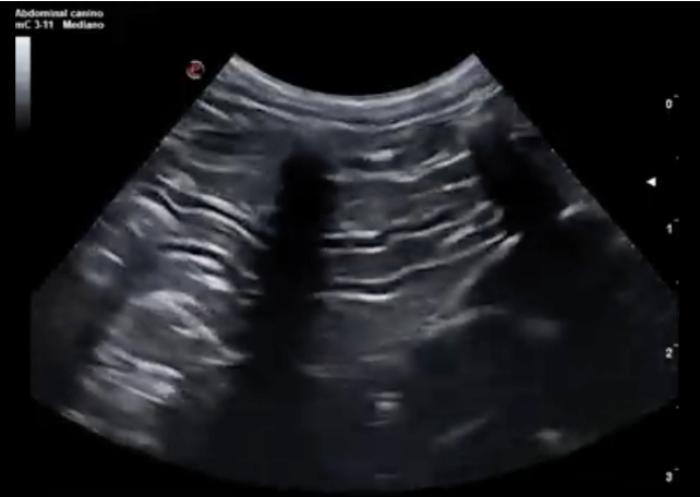

Comenzaremos posicionando el transductor perpendicular a las costillas en uno de los espacios intercostales, pudiendo evaluar al menos el espacio entre dos costillas, la línea PP y no más de 2-3 cm de profundidad de campo (Figura 1A-B).